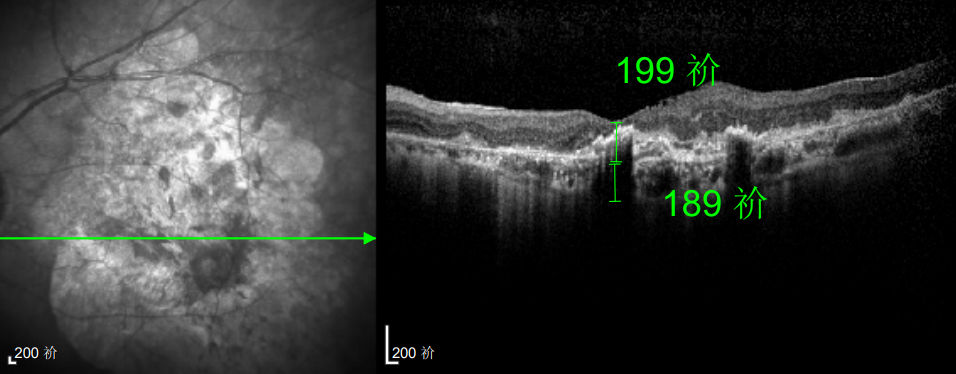

△延誤復查后的左眼

△規(guī)劃化治療后的左眼